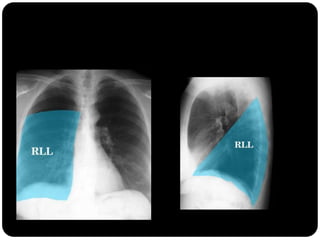

Atelectasia do Lobo Médio

Impacto mínimo

sobre volume total

do hemisfério

direito (é o menor

dos lobos) LS e LI

inferior compensam

a perda de volume;

Atelectasia lobo

inferior direito

Observar:

Sinal de Luftsichel

Elevação

hemidiafrgma

esquerdo

Sinal da silhueta

(língula atelectasiada

também)

Atelectasia do lobo

inferior esquerdo

Atelectasias de lobos

inferiores deslocam

o hilo posterior e

medialmente;